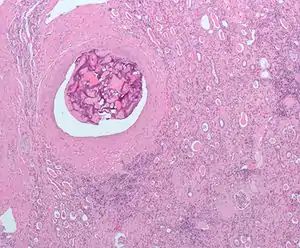

| Micrograph of embolic material in the artery of a kidney. The kidney was surgically removed because of cancer. H&E stain. | |